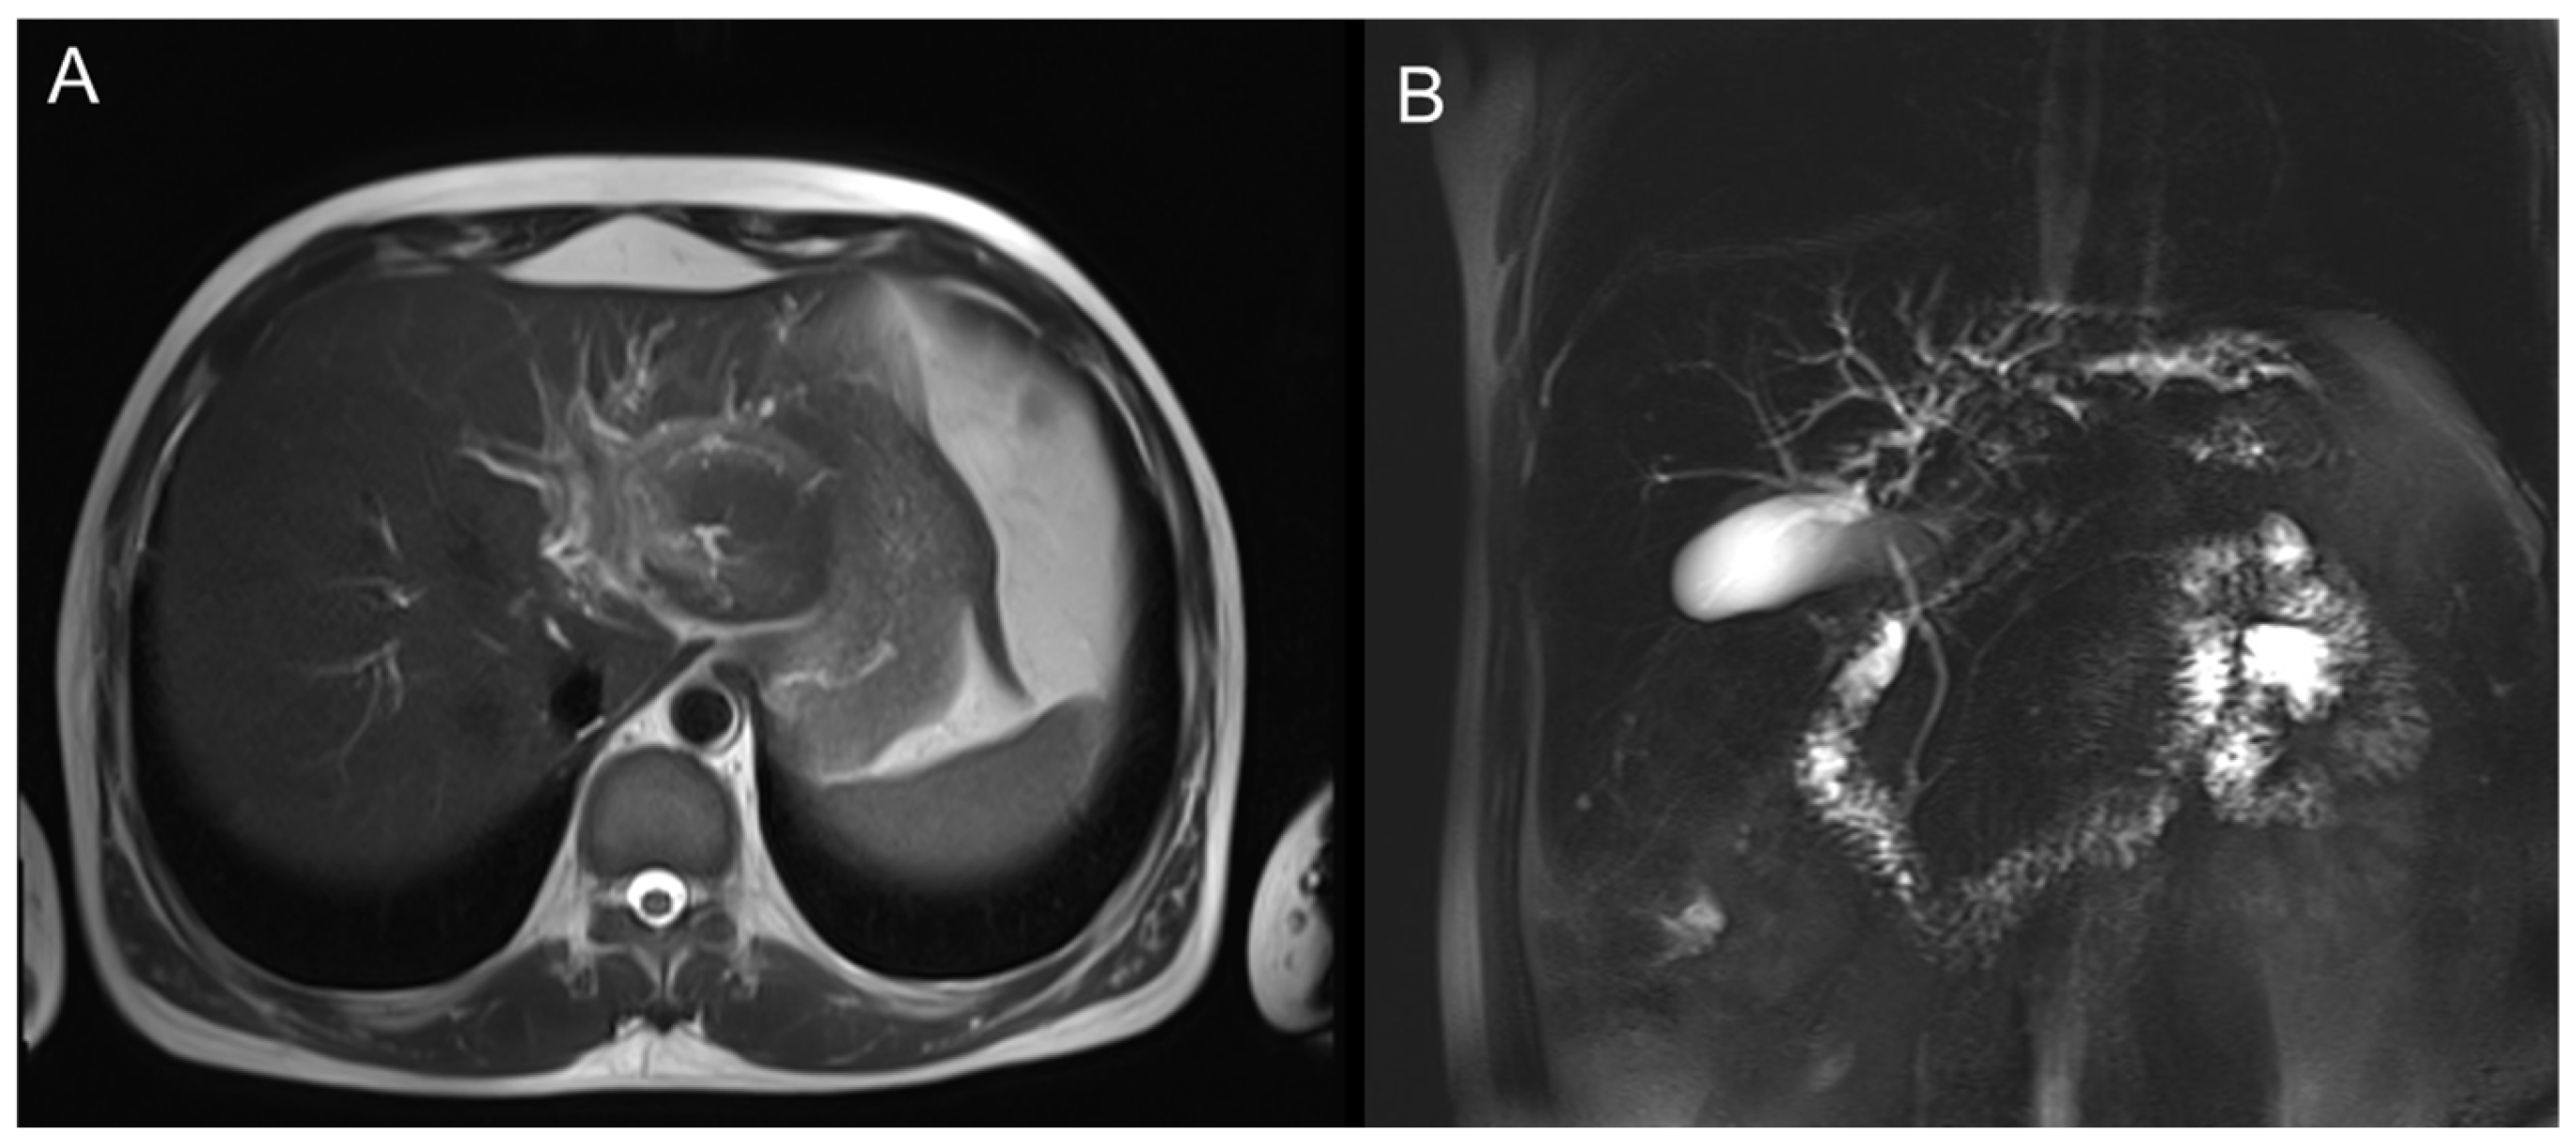

MRI showed a mass-like lesion in the left hepatic hilum, about 30 × 22 mm, with ill-defined borders and marked enhancement after contrast. Dilatation of intrahepatic bile ducts and multiple enlarged lymph nodes in the hepatic hilum were also observed (Figure 2).

The left hepatic lobe near the hilum shows a mass-like lesion with slightly high signal intensity on T2WI and mild perilesional edema.

Figure 2. Axial T2-weighted MR images of the liver. (A) Axial view demonstrating a well-defined hilar lesion with dilated intrahepatic bile ducts. (B) Coronal view showing the hepatic hilar mass with intrahepatic biliary dilatation and gallbladder distension.